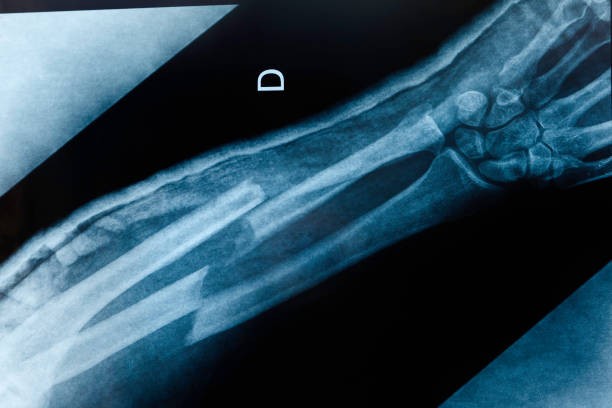

What Happens When a Bone Breaks?

When a bone fractures, the body reacts instantly like it’s handling an emergency. Blood vessels around the site break, forming a clot that stabilizes the area. Inflammation soon follows, clearing damaged tissue and starting the repair process. This chain reaction prepares the ground for new tissue and, eventually, strong bone to grow back.

At the same time, surrounding muscles and soft tissues help protect the injured site. While this early stage can be painful, it is the body’s natural way of preparing for the step-by-step healing that follows.